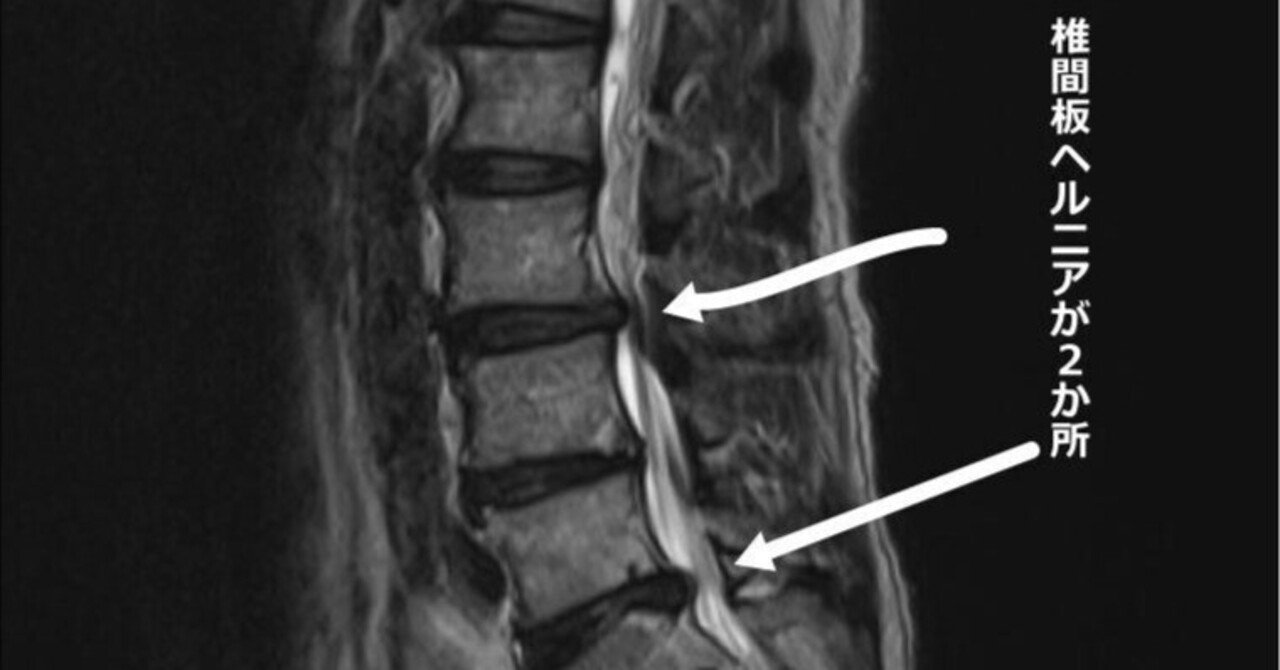

- 磁気共鳴画像法 (MRI): MRI は、椎間板自体だけでなく、脊髄と神経根の 3D 画像を生成します。